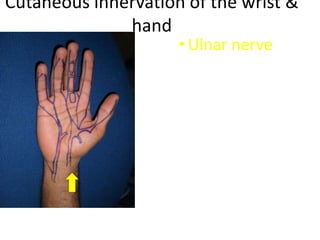

- Naming the bones, joints, tendons, nerves and skin landmarks of the hand and wrist.